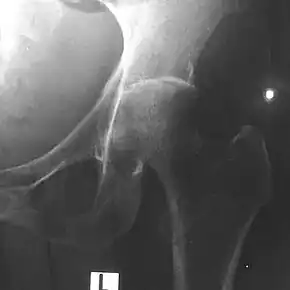

Depending on the course of infection, other severe manifestations develop. About 1 to 5% of those infected develop inflammation of the brain and brain covering or collection of pus in the brain; 14 to 28% develop bacterial inflammation of the kidneys, kidney abscess or prostatic abscesses; 0 to 30% develop neck or salivary gland abscesses; 10 to 33% develop liver, spleen, or paraintestinal abscesses; 4 to 14% develop septic arthritis and osteomyelitis.[1] Rare manifestations include lymph node disease resembling tuberculosis,[9] mediastinal masses, collection of fluid in the heart covering,[3] abnormal dilatation of blood vessels due to infection,[1] and inflammation of the pancreas.[3] In Australia, up to 20% of infected males develop prostatic abscess characterized by pain during urination, difficulty in passing urine, and urinary retention requiring catheterisation.[1] Rectal examination shows inflammation of the prostate.[3] In Thailand, 30% of the infected children develop parotid abscesses.[1] Encephalomyelitis can occur in healthy people without risk factors. Those with melioidosis encephomyelitis tend to have normal computed tomography scans, but increased T2 signal by magnetic resonance imaging, extending to the brain stem and spinal cord. Clinical signs include: unilateral upper motor neuron limb weakness, cerebellar signs, and cranial nerve palsies (VI, VII nerve palsies and bulbar palsy). Some cases presented with flaccid paralysis alone.[3] In northern Australia, all melioidosis with encephalomyelitis cases had elevated white cells in the cerebrospinal fluid (CSF), mostly mononuclear cells with elevated CSF protein.[9]